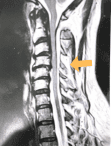

William J. Sonstein, M.D., F.A.C.S. is a Board-Certified Diplomate, American Board of Neurosurgery. He has a special interest in complex spine surgery and has one of the largest experiences with Posterior Lumbar Interbody Fusion (PLIF) on Long Island. This procedure relieves pain for patients with intractable back pain. Dr. Sonstein uses minimally invasive procedures whenever possible, such as Kyphoplasty and X-STOP™ to treat spinal compression fractures and spinal stenosis.

Case Studies